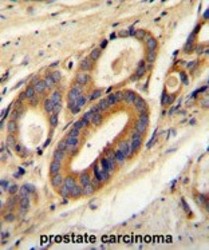

AP50303PU-N IHC

Method: Other validation